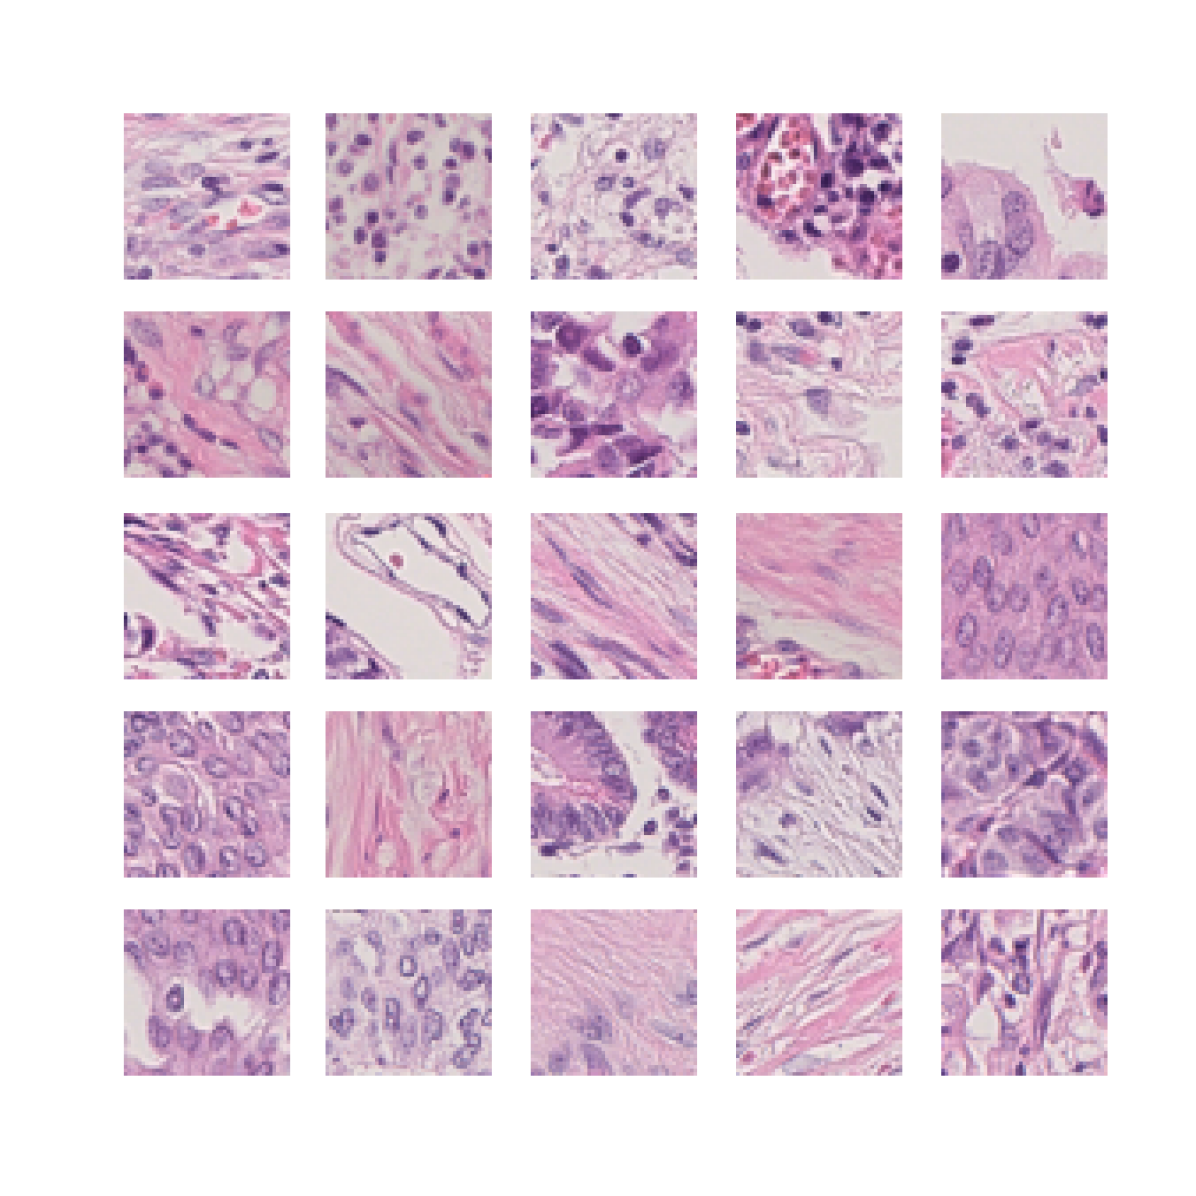

We also analyse the activation maps for each model using GradCAM as described in section S3. This offers more insight into the areas of the image which are contributing most heavily to the models’ representations. In Figure 4(b) we present some representative examples, however, a larger selection which was chosen at random is presented in Figures S10 to S25. The larger selection makes it easier to see the emergent patterns, including that privileged Siamese models tend to mainly identify features which are strongly present in both inputs, while unprivileged Siamese models tend to learn more diffuse features that are not specific to one cell phenotype or image region. TriDeNT ♆ incorporates both sets of features, learning both features specific to the privileged data and more the general features associated with unprivileged Siamese networks.

S1.1 Histology

To analyse tissue samples, pathologists take slices of tissue around 5m thick to be analysed under a microscope. To make it easier to identify different structures, the slide is typically stained with chemicals that bind tightly to different components of the sample, dying them different colours. By far the most common staining method used in histopathology is haematoxylin and eosin (H&E) staining. Haematoxylin stains components that are rich in nucleic acids, such as nuclei and ribosomes, while Eosin stains common protein structures pink, such as connective tissue, collagen, and the cytoplasm [54].

Immunohistochemistry is an ancilliary staining technique often used in medical diagnosis, which works by using an antibody to target specific proteins in tissue. Secondary chemical processes are coupled to the antibody to produce a colour, making it much easier to identify their presence and location within tissue. There are many different antibodies used which each target a specific protein or protein type. Common examples of antibody targets include cytokeratins, which are found in epithelial cells, CD3, CD4, and CD20, which are found in various types of immune cells, and smooth muscle actin (SMA), which is found in myofibroblasts [55].

Typically these stains are highly informative about one particular protein of instance, but lack the generality of H&E staining. Consequently, they are primarily used as secondary sources of information to assist with research or diagnosis.